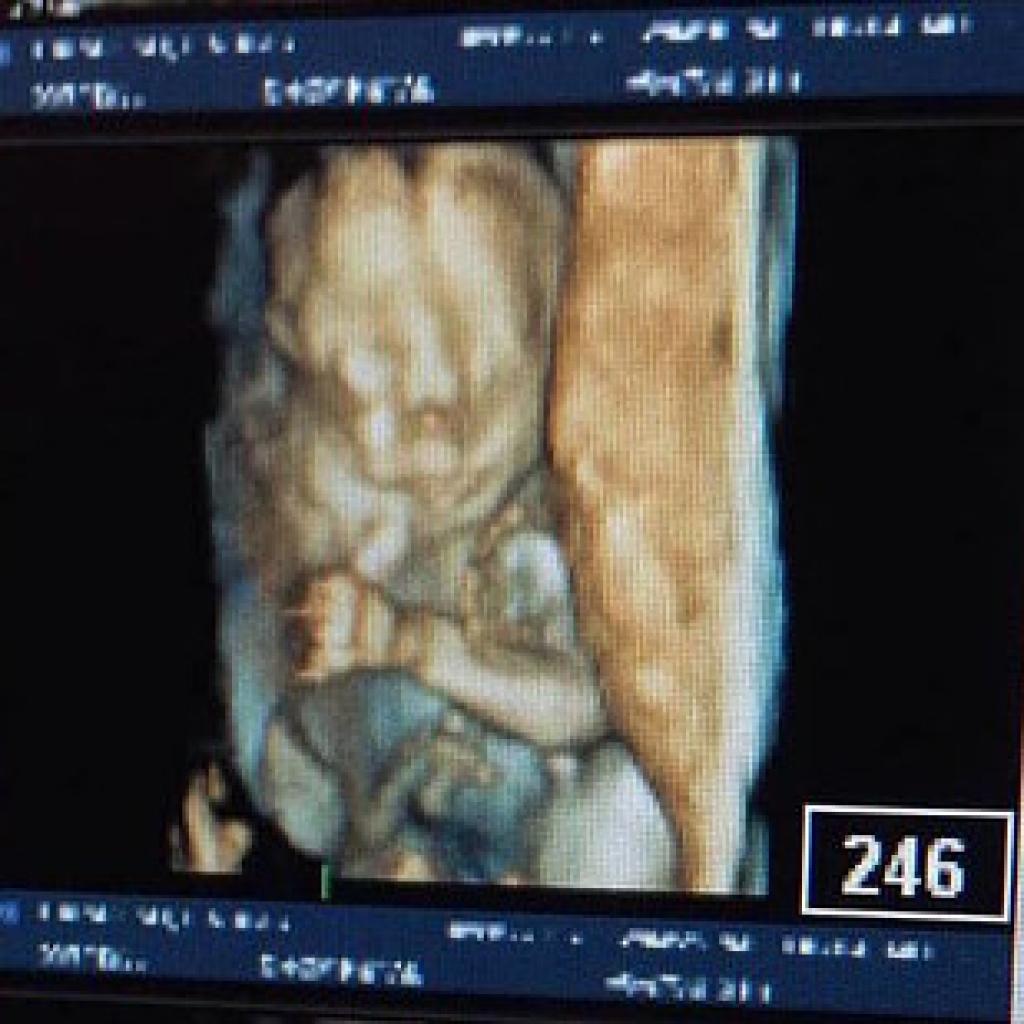

Lindsey était enceinte de 18 semaines en février 2016 quand lors d’une échographie, on découvre une masse sur le cou du bébé.

« Le médecin nous a dit qu’il valait mieux avorter car sa mort était inévitable, mais on voulait laisser une chance à Omara. » Alors, ils ont attendu jusqu’à ce qu’elle ait 27 semaines pour l’accoucher par voie chirurgicale. Mais à peine trois semaines plus tard, un IRM a confirmé que la tumeur avait triplé de taille et se propageait dans sa tête, son torse, ses poumons et ses yeux.

Il s’agissait d’une malformation lymphatique très agressive, et s’avérait fatale.

La tumeur tuerait l’enfant avant 27 semaines, et Lindsey n’aura pas le choix de délivrer l’enfant, la tumeur étant trop grande pour la procédure prévue.

« Quand elle est sortie, on a pu voir la tumeur, nous en avons été choqués. »

Dans cette photo, la tumeur a été drainée et sa taille réduite.